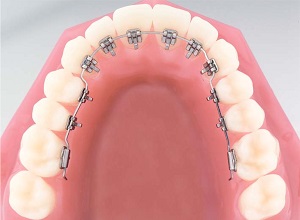

Görünmeyen Ortodontide Diş Telleri İçeriden TakılırGizli Ortodonti

Görünmeyen Ortodontide Diş Telleri İçeriden TakılırGizli Ortodonti